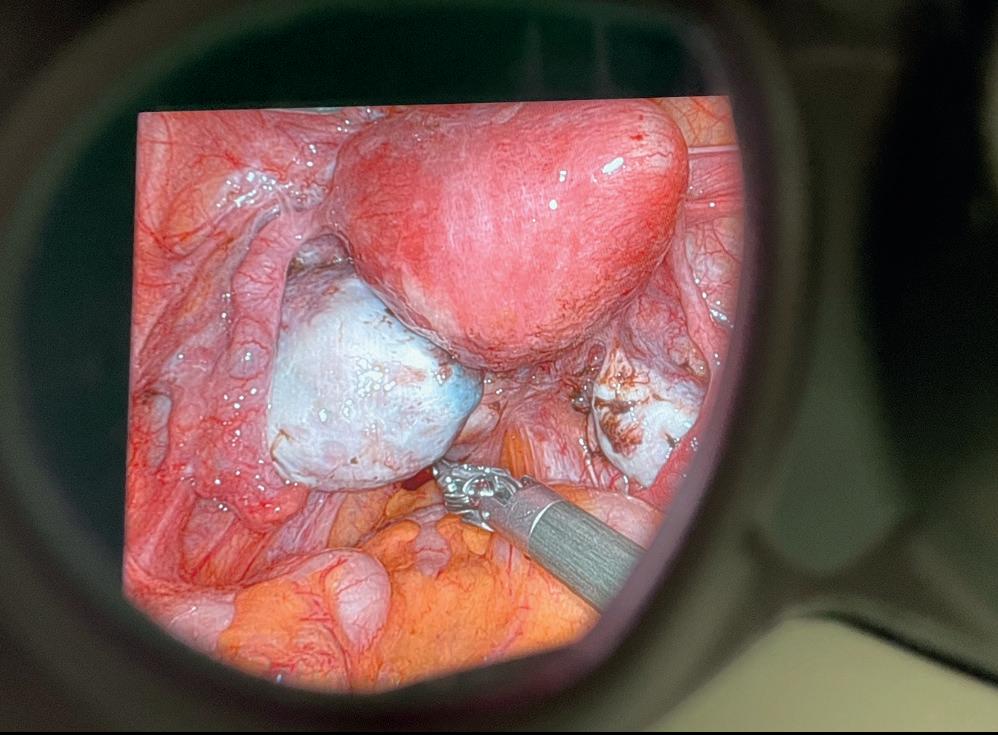

Uterusmanipulatorer fra CooperSurgical

Advincula Delineator uterusmanipulator til bruk ved laparoskopisk hysterektomi Optimal kontroll og sikkerhet ved gynekologiske inngrep. Våre uterusmanipulatorer gir maksimal presisjon for kirurger og økt komfort for pasienten

Advincula Delineator

Engangs Tre størrelser Sterk og kraftig